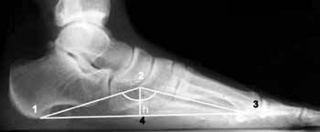

С помощью рентгена можно визуализировать высоту и углы свода стопы, выявить аномалии костной ткани и суставов. Диагностика позволяет выявить наличие деформации и определить степень ее развития.

Рентгенологическое исследование является основным методом диагностики плоскостопия и других патологий дистального отдела стопы. Фотографии делаются в нескольких проекциях — прямой (стопа пациента на весу) и боковой (с дополнительным рентгеном голеностопного сустава). Процедура не связана с повышенным риском облучения; доза облучения за сеанс составляет от 0,05 до 0,1 мЗв, что является относительно низким показателем.

Выделяют три типа продольного плоскостопия, которые различаются выраженностью симптомов и изменений:

- Первый тип. В начальных стадиях деформации патология слабая, а угол наклона продольного свода стопы колеблется от 130 до 140˚. Визуально определить деформацию невозможно. Пациенты жалуются на симптомы, связанные с чувством усталости после продолжительной ходьбы и периодическими отеками в области стоп. Четкого болевого синдрома нет, есть небольшая болезненность при надавливании на дистальный отдел стопы.

- Второй тип. Деформация выражена умеренно, при испытании угол наклона дуги составляет от 141 до 156 15. Наблюдается видимое уплощение стоп, а при детальном диагнозе — артритные изменения плюсневых костей. Болевой синдром обостряется даже после незначительных физических нагрузок. При этом боль распространяется на всю голень, вплоть до бедра.

- Третий тип. Для этого типа характерно выраженное плоскостопие, когда угол дуги превышает 157˚. Клинические симптомы включают постоянную боль, отек ног, остеоартрит и затруднения движений. Пациенту нельзя носить обычную обувь, и необходимо срочно носить специальную ортопедическую обувь. В запущенных случаях происходит деформация щиколоток.

Обратите внимание, что правильный угол дуги должен составлять 125–130, что указывает на отсутствие деформации.